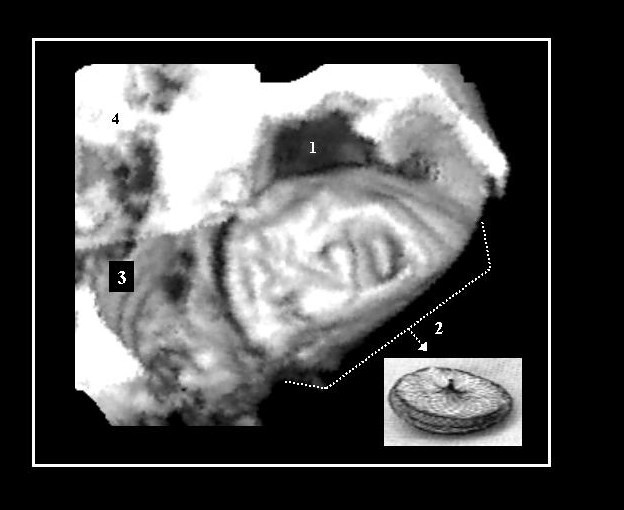

Unroofed coronary sinus atrial septal defect 2d and 3d echo.

Coronary sinus septal defect (unroofed coronary sinus ...

Coronary sinus septal defect (unroofed coronary sinus ... from els-jbs-prod-cdn.jbs.elsevierhealth.com